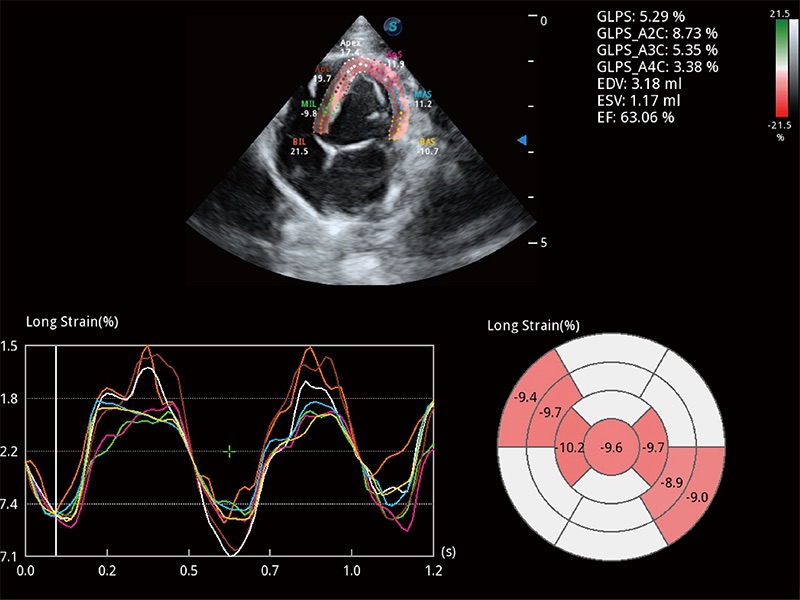

通過心肌識別技術(shù)與二維斑點(diǎn)追蹤技術(shù)相結(jié)合,對心臟的超聲圖像進(jìn)行量化分析。計算心肌17個節(jié)段的應(yīng)變、應(yīng)變率、速度、位移等,并通過牛眼圖的形式進(jìn)行呈現(xiàn)。